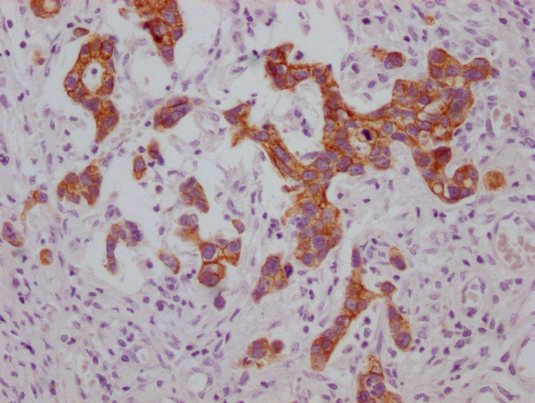

IHC image of CSB-MA974483 diluted at 1:100 and staining in paraffin-embedded human gastric cancer performed on a Leica BondTM system. After dewaxing and hydration, antigen retrieval was mediated by high pressure in a citrate buffer (pH 6.0). Section was blocked with 10% normal goat serum 30min at RT. Then primary antibody (1% BSA) was incubated at 4°C overnight. The primary is detected by a Goat anti-mouse IgG polymer labeled by HRP and visualized using 0.05% DAB.